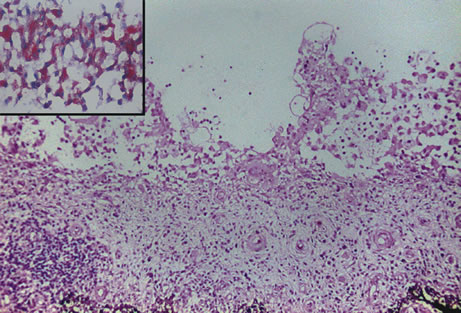

Retinochoroiditis

Necrotizing retinitis with secondary choroiditis is seen in protozoal infections such as toxoplasmosis or in herpetic infections. Infection with Toxoplasma gondii leads to retinitis and secondary choroiditis (Fig. 25), usually granulomatous.127 Congenital infection can be acquired in utero by transplacental transmission of the parasite from the infected mother to the fetus.128 Acquired disease occurs after ingestion of oocysts or tissue cysts.129–132 The congenital form of infection leads to atypical macular colobomas. Reactivation of the infection is caused by release of organisms that have remained dormant in the margins of old congenital retinal scars.133 The slowly proliferating form of the organism, termed the bradyzoite, can be seen in cysts. The rapidly multiplying form, termed the tachyzoite, may be difficult to identify in an infected retina or in immunocompetent individuals, but they are frequently seen in the retinitis of immunocompromised hosts.134 Active infection usually causes focal retinal opacification and an intense vitritis. These findings may give the appearance of a “headlight in a fog” in an immunocompetent person. In contrast, this clinical presentation is rare in patients with AIDS, in whom diffuse retinitis is observed with non-granulomatous choroiditis.134

Fig. 25. Toxoplasma retinochoroiditis. Necrotic retina shows cysts of toxoplasma gondii, and the choroid reveals granulomatous inflammation. (Hemotoxylin-eosin ×65.) Inset (Gomori methenamine silver ×160) shows cysts of the organisms.